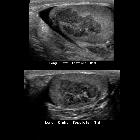

Newborn with

ambiguous genitalia. Sagittal (above) and transverse (below) US of the kidneys shows enlarged hypoechoic lesions superior to the kidneys which have a triangular shape on sagittal images and a cerebriform shape on transverse images.The diagnosis was congenital adrenal hyperplasia.